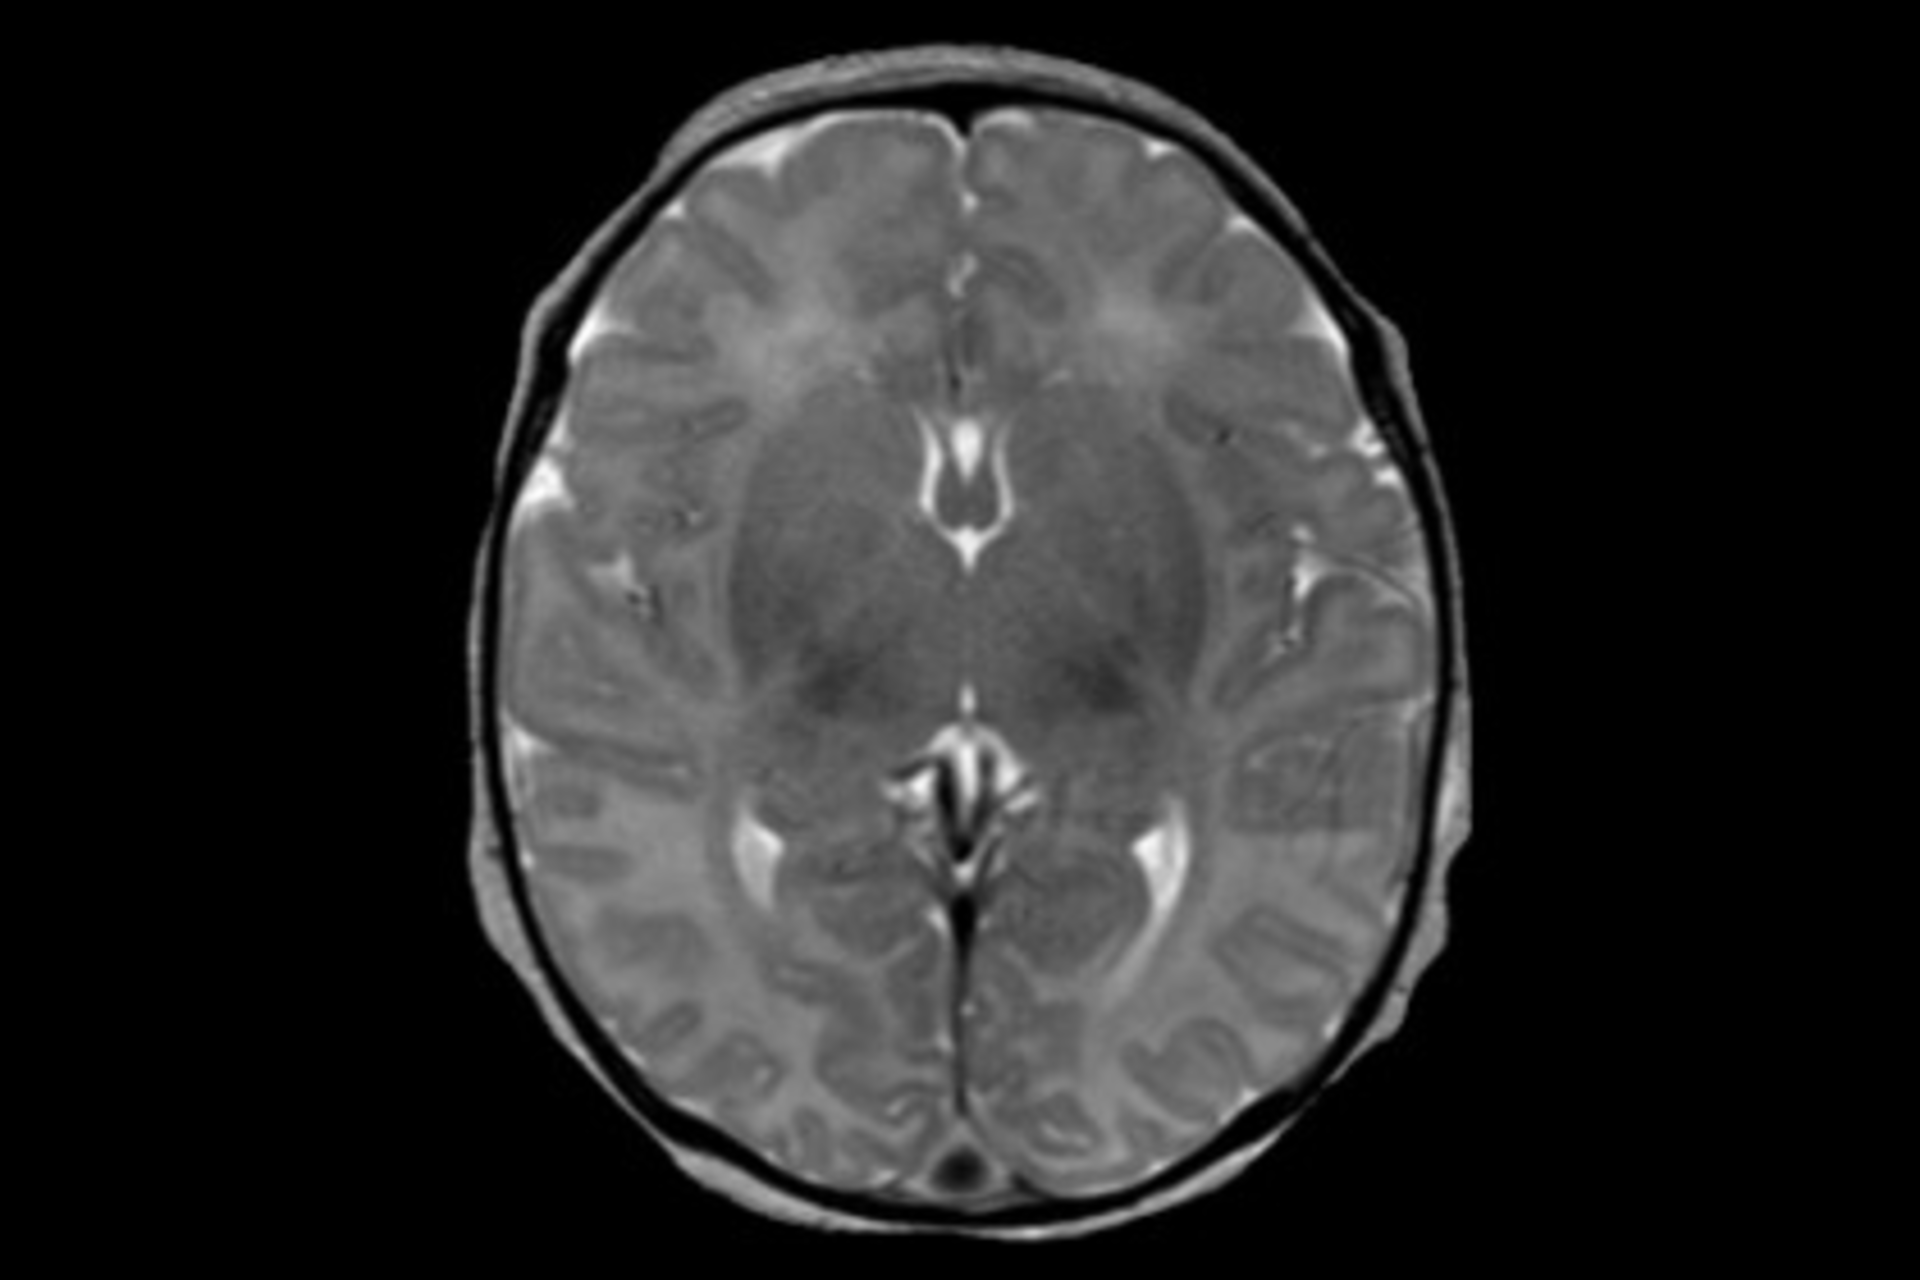

Researchers at Johns Hopkins are building a digital library of MRI scans from children with normal and abnormal brains in an effort to give doctors a Google-like search system to improve how they diagnose and treat these pediatric patients with brain disorders.

The researchers store the images in the cloud. Ultimately, the search system will allow physicians to access thousands of pediatric scans to look for any that resemble their own patient's image. For funding, Hopkins has received a three-year, $600,000 grant from the National Institutes of Health (NIH).

Susumu Mori, Ph.D., a professor of radiology in the Johns Hopkins School of Medicine, is working with Miller on the project. He and Thierry Huisman, M.D., a professor of radiology and pediatrics and the director of pediatric radiology at the Johns Hopkins Children's Center, in four years have created a clinical database of more than 5,000 whole-brain MRI scans of children treated at Johns Hopkins. They have withheld identifying information, but included medical conditions. The software has indexed anatomical information involving up to 1,000 structural measurements in 250 regions of the brain, sorted into 22 brain disease categories.